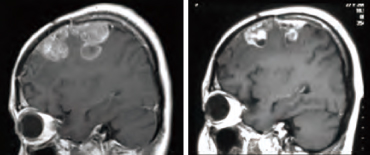

悪性脳腫瘍、特に悪性神経膠腫はBNCT 臨床研究で期待の大きい対象です。BNCTでは一度に大線量の照射が可能なため、X線治療では経験できない早期(2日程度)に劇的な腫瘍の反応(MRI画像の造影病巣の縮退・消失)が散見されます(図:大阪医大症例)。